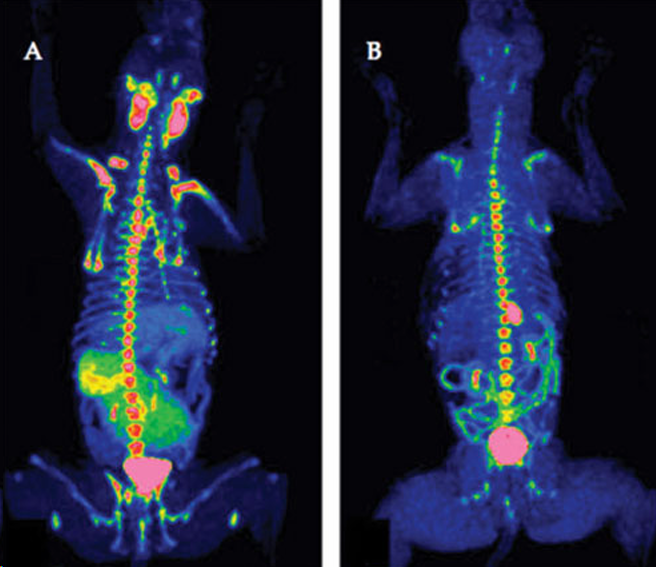

PET o Positron Emission Tomography

- Escaso uso en medicina veterinaria

- La mecánica es similar que la gammografia pero no es radiación gamma sino beta

- Imagen tomográfica (corte axial)

- Muy específico para el diagnóstico de cáncer

- PET poco comun en veterinaria aunque en investigación si se usa. Se está haciendo cada vez mas comun en medicina.

**PET TC o Tomografía por Emisión de Positrones – Tomografía Computarizada

- Valoramos la via glicolítica de la glucosa Las células tumorales tienen un metabolismo muy incrementado Captan la glucosa marcada

- Unidades SUV (standard uptake value). Si son > 2.5 ó 3 = NEOPLASIA